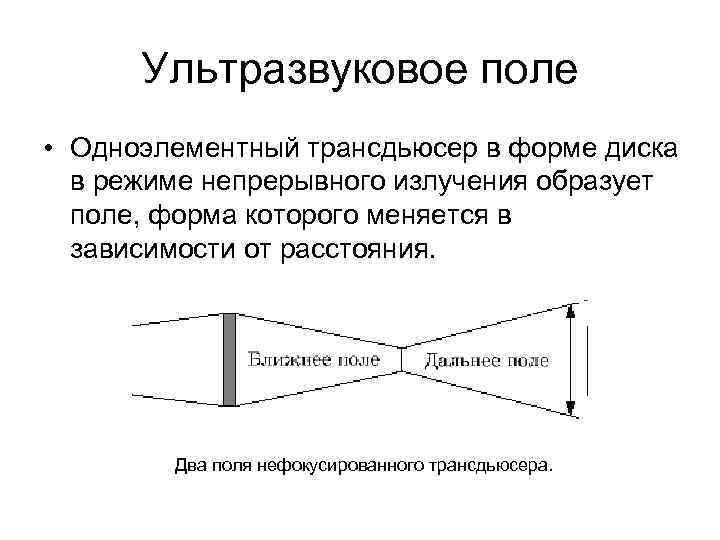

Ультразвуковое поле • Одноэлементный трансдьюсер в форме диска в режиме непрерывного излучения образует поле, форма которого меняется в зависимости от расстояния. Два поля нефокусированного трансдьюсера.

Ультразвуковое поле • Одноэлементный трансдьюсер в форме диска в режиме непрерывного излучения образует поле, форма которого меняется в зависимости от расстояния. Два поля нефокусированного трансдьюсера.